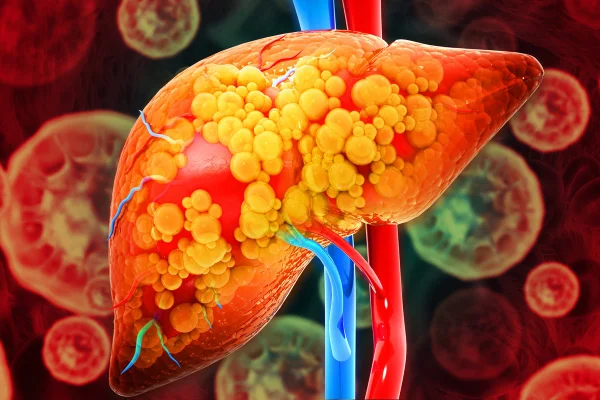

A esteatose hepática é popularmente conhecida como gordura no fígado

Mohammed Haneefa Nizamudeen/Getty Images

A condição de gordura no fígado acomete 30% da população mundial, segundo o artigo

Magicmine/Getty Images

No início, as manifestações costumam ser inespecíficas, como cansaço, fraqueza, perda de apetite, náuseas, sensação de inchaço abdominal ou desconforto do lado direito do abdome

Magicmine/Getty Images